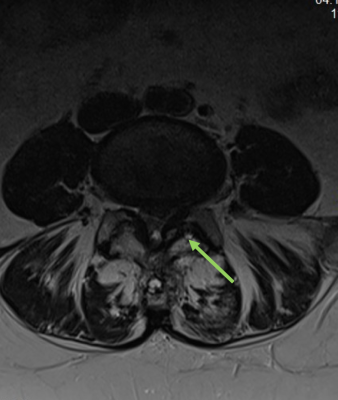

Zervikaler/Lumbaler Bandscheibenvorfall

Im Rahmen degenerativer Verschleißprozesse der Bandscheibe kann es zum Austritt von Bandscheibengewebe in den Wirbelkanal kommen. Durch Bedrängung der dort verlaufenden Nerven kommt es abhängig von der Schädigungshöhe zu Schmerzen, Taubheitsgefühl und Lähmungserscheinungen im Bereich der Arme bzw. Beine. Wird das Rückenmark selbst durch den Druck der Bandscheibe geschädigt, so können Blasen-Mastdarmstörungen oder gar eine Querschnittlähmung auftreten.

Im Normalfall kann der lumbale Bandscheibenvorfall minimalinvasiv mit Hilfe des Mikroskops entfernt werden, ohne dass eine Stabilisierung der Wirbelsäule notwendig ist.

Spinalkanalstenose

Die Spinalkanalstenose ist eine zunehmende dynamische Einengung des Wirbelkanals auf Bandscheibenniveau durch überwiegend degenerative Veränderungen der Bandscheibe, der Wirbelkörperendplatten, der Zwischenwirbelgelenke sowie der umgebenden Bandstrukturen mit und ohne begleitende Instabilität des betroffenen Bewegungssegmentes. Die Lendenwirbelsäule ist hiervon häufiger als die Halswirbelsäule betroffen.